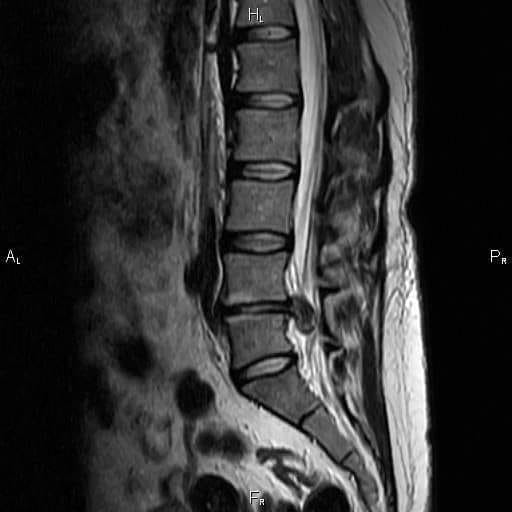

Грыжа 9мм

Грыжа 9мм 107 фото